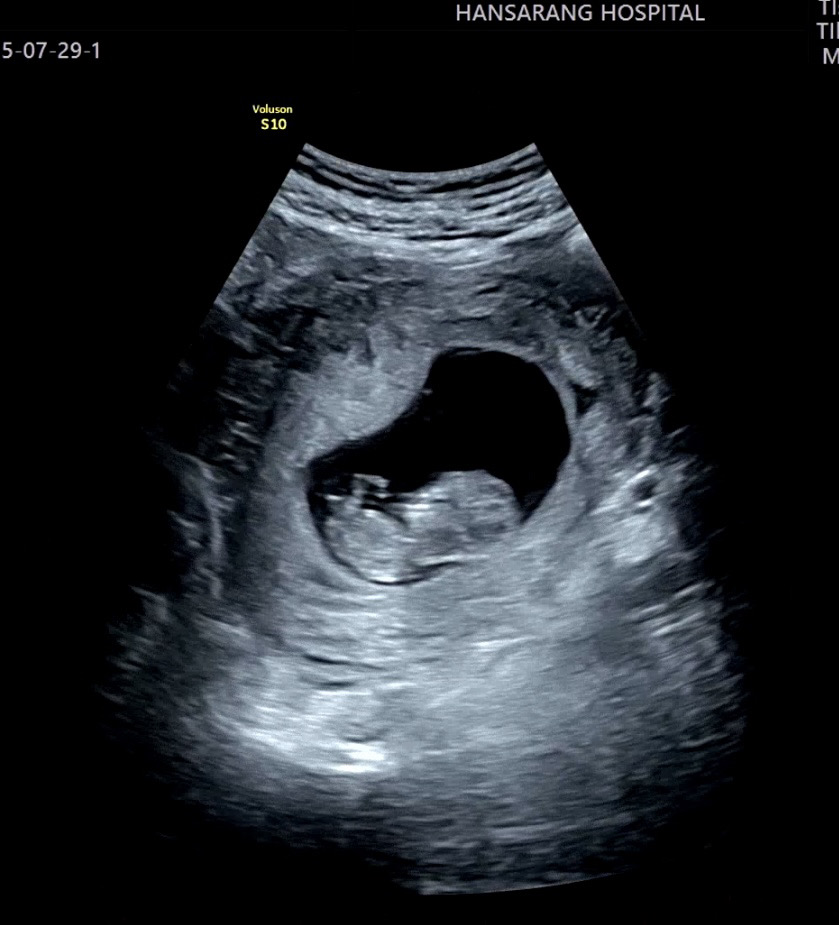

7주 차엔 울렁거림 토덧 심했는데 8주차부터 아무 증상이 없어요...체한 느낌도 울렁거리는 느낌도 피곤하지도 않네요 그렇다고 먹덧도 아니고 이럴수가 있나유????? 오늘 병원가서 아가 심장소리 초음파 모두 잘 확인했는데 아무런 증상이 없으니 괜스레 찝찝한 느낌이에요🥹 입덧이나 피곤함 아예 없으신 산모분들 계신가용?? 10주차부터 엄청 심해진대서 긴장하고 있었는데 정말 아무런 증상이 없으니 신기하고 먼가 찜찜하네요ㅠㅠㅠㅠㅠ